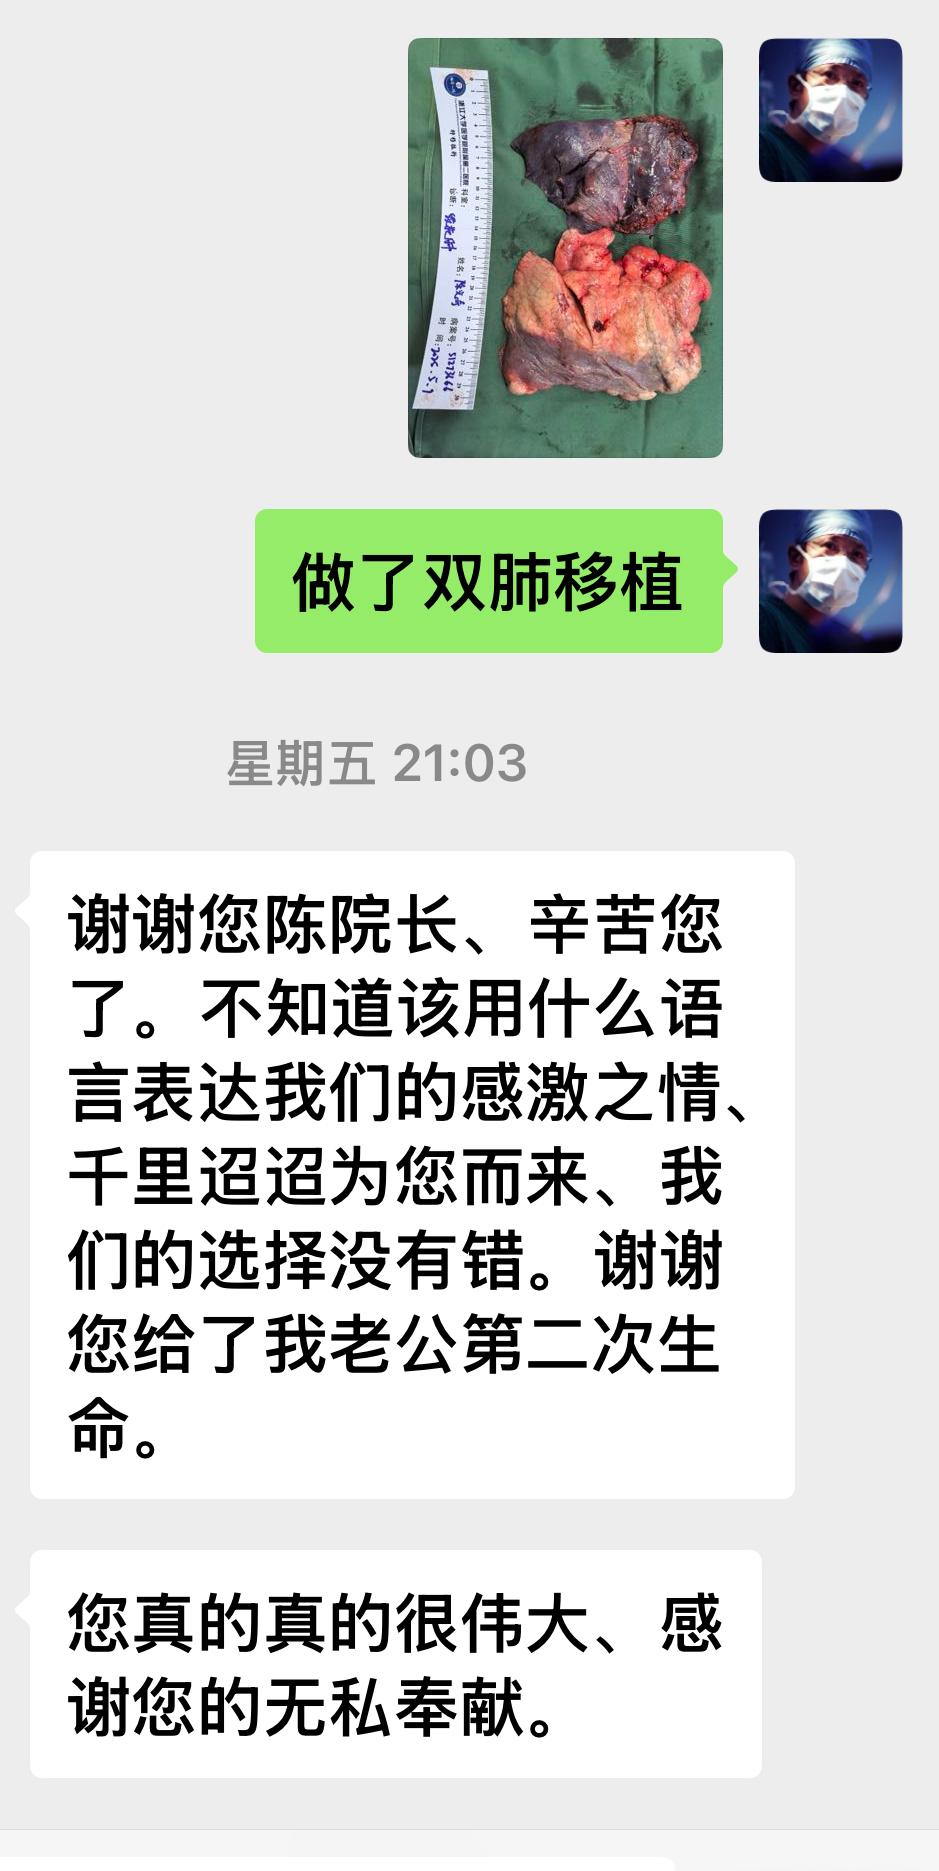

职业病导致的肺损伤,除了晚期尘肺病人做肺移植以外,最近我连续做了3例工作时不慎吸入有毒气体导致的肺损伤肺毁损。这位受者,30岁,吸入硫化氢肺损伤二年了,一直保守治疗,但患者逐渐呼衰,一侧肺毁损、一侧肺气肺。最近在浙二双肺移植术后仅二天,就己行走进行康复锻练,这类受者因为年轻,如果早点接受移植,大都能快速康复。但最近ICU又收治了一位受者,吸入“氟中毒”肺实变纤维化(图4),目前ECMO已维持一个月才想到来求助肺移植,目前濒危,可能会等不到供肺,没有机会救治。

职业病导致的肺损伤,除了晚期尘肺病人做肺移植以外,最近我连续做了3例工作时不慎吸入有毒气体导致的肺损伤肺毁损。这位受者,30岁,吸入硫化氢肺损伤二年了,一直保守治疗,但患者逐渐呼衰,一侧肺毁损、一侧肺气肺。最近在浙二双肺移植术后仅二天,就己行走进行康复锻练,这类受者因为年轻,如果早点接受移植,大都能快速康复。但最近ICU又收治了一位受者,吸入“氟中毒”肺实变纤维化(图4),目前ECMO已维持一个月才想到来求助肺移植,目前濒危,可能会等不到供肺,没有机会救治。